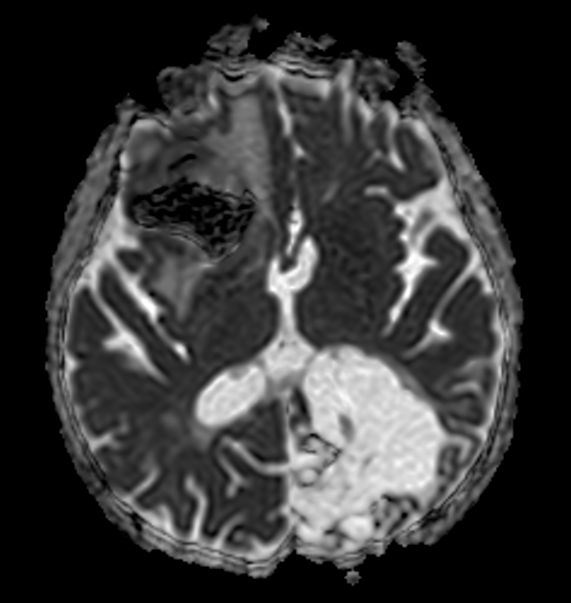

Axial SWIp (Modulus)

Axial SWIp (minIP)

Axial SWIp (Phase)